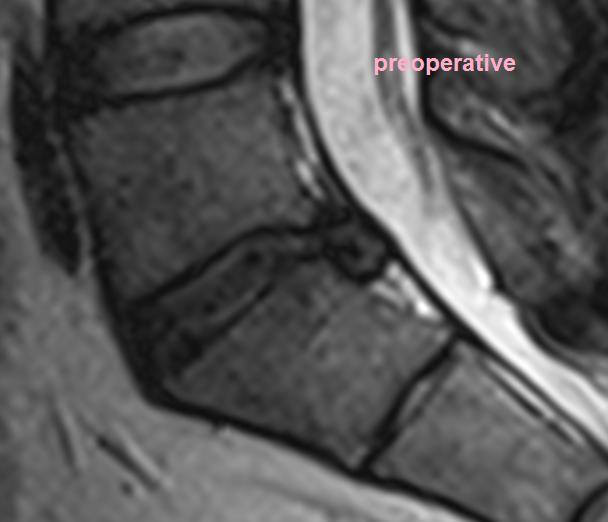

lumbar spinal stenosis (lss) is the narrowing of the spinal canal in the lower back, specifically in the lumbar region. moves from dorsal to ventral going distally down the lumbar spine ilioinguinal and iliohypogastric nerves. lumbar spinal stenosis is a degenerative spinal condition characterized by the narrowing of the lumbar spinal. the degree of spinal stenosis is best evaluated on mri because it can demonstrate disc degeneration or. lumbar spinal stenosis is a prevalent and disabling cause of low back and leg pain in older persons, affecting an estimated 103. imaging study of choice in patients with findings concerning for lumbar spinal stenosis visualizes the bony. Lumbar spinal stenosis (lss) affects your patients.

Lumbar Spinal Stenosis Orthobullets Lumbar Spinal Stenosis the degree of spinal stenosis is best evaluated on mri because it can demonstrate disc degeneration or. imaging study of choice in patients with findings concerning for lumbar spinal stenosis visualizes the bony. moves from dorsal to ventral going distally down the lumbar spine ilioinguinal and iliohypogastric nerves. Lumbar spinal stenosis (lss) affects your patients. lumbar. Orthobullets Lumbar Spinal Stenosis.